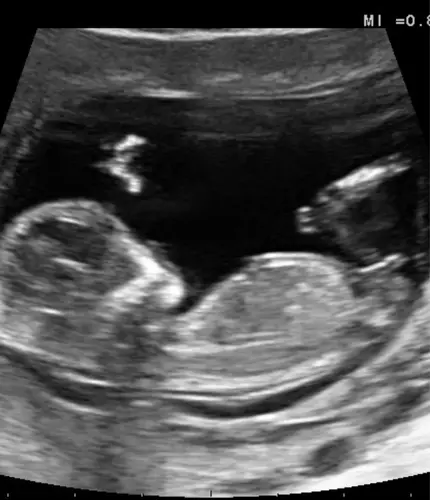

Ik heb deze vanmiddag geplaatst in het andere topic, is met 13+1. Ik heb 1 reactie ontvangen, zijn er nog mensen die een uitspraak kunnen/willen doen op basis van de nub? 🥰

Misschien helpt dit. De echopraktijk voor pretecho’s zegt bij deze echo een meisje omdat de nub vlak loopt aan het einde.